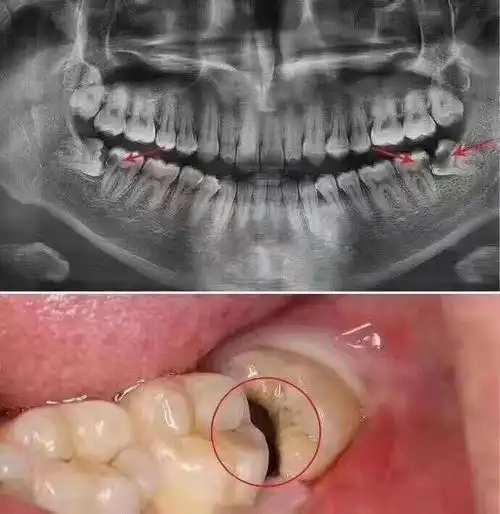

阻生智齿(尽头牙)的危害 - 美篇